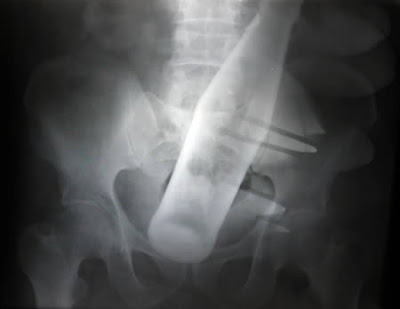

The Most Bizarre X-Rays

This X-ray was taken of a 60-year-old man who checked himself into Nishtar Hospital in Multan, Pakistan. He sought treatment because he claimed thieves had inserted a Pepsi bottle into his anus before stealing two of his buffalo.